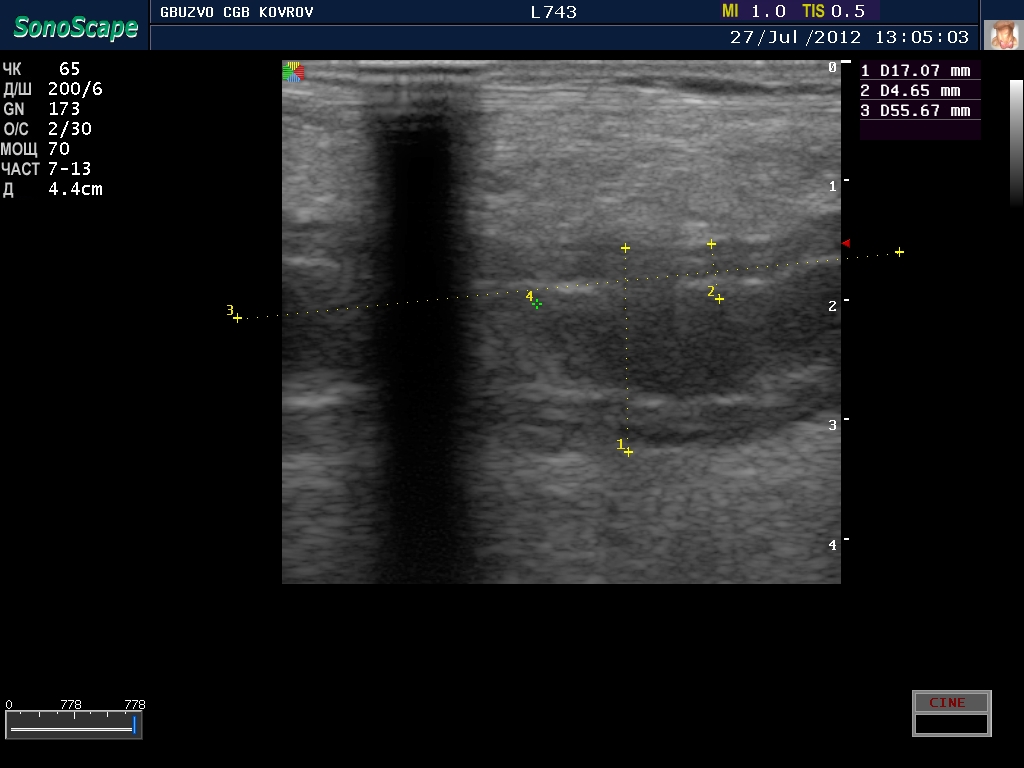

полечили два дня в гастроэнтерологии...состояние ухудшилось, узи контроль----->

поподробнее? :shock: бодимаркер находится в правой подвсздошной области, я бы подумал про аппендикс 8-)